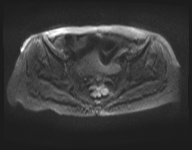

5.jpeg

轴位

ADC

中下段直肠肿块,形态不规则,边缘清晰,质地不均一,以囊性为主,多分叶,增强扫描时实性部分强化,弥散不受限,病灶下缘位于肛门直肠连接处30毫米处,呈半圆形,横跨半径3点至9点方向,纵轴长约44毫米,向直肠系膜脂肪方向延伸达15毫米,但未超过直肠系膜筋膜。直肠上段无改变。未观察到淋巴结肿大。

此外,可见子宫呈前屈状,外观不均匀,内部信号低,呈卵圆形,边缘清晰,造影剂应用后出现不均匀强化,从而影响了子宫内膜的体积效应。子宫横、前后和头尾方向的尺寸分别为 2.9 x 2.8 x 4.0 cm,与黏膜下肌瘤相关。